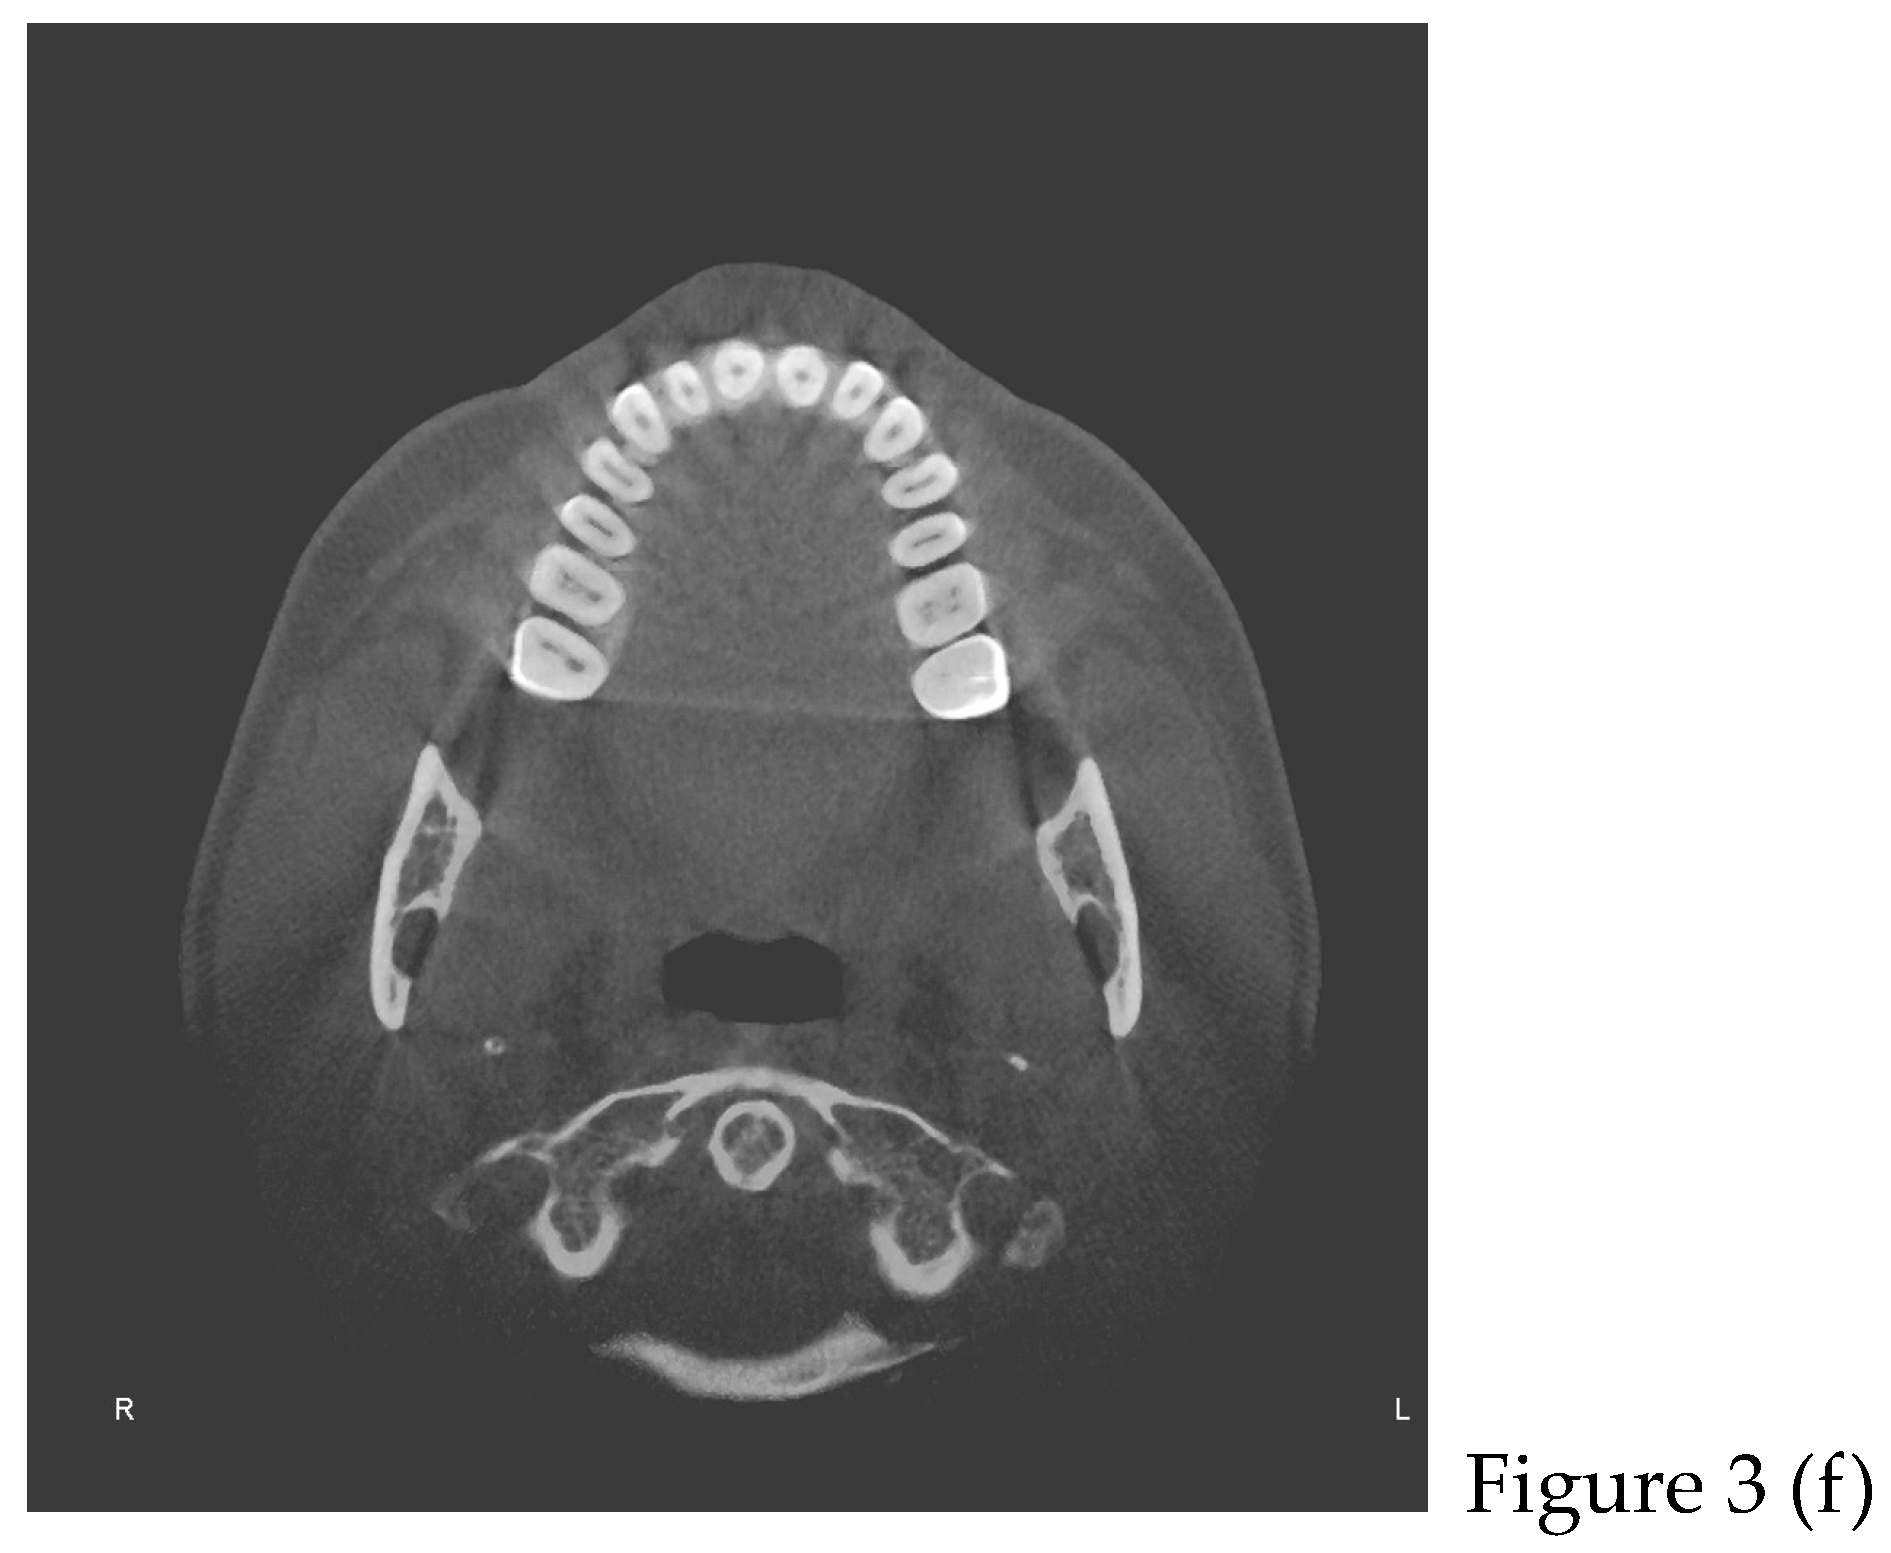

2.2. Cone Beam CT Analysis

| CBCT (t0) | |

| after 8 months | Retainers + CBCT (t1) + final photos |